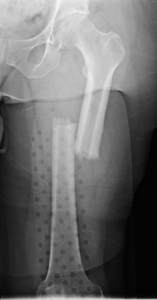

The thigh bone is a mostly tubular structure throughout its length. The tubular portion is termed the femoral shaft. Fractures of the shaft of the femur most commonly occur from a high energy mechanism in younger people, whereas they can more commonly occur from a low energy injury in elderly people with poor bone quality. Treatment often consists of a rod that is placed down the central portion of the femur (also known as the femoral canal), and this rod is secured to the bone at both ends with screws. Typically, this rod will provide enough support to allow some weight bearing even before the bone has healed (the orthopaedic surgeon will determine weight bearing status on a case by case basis, however).

Femoral shaft fractures can also occur in individuals who have had previous orthopaedic surgery, such as hip replacement. In this instance, there is already a device occupying the femoral canal (the hip stem). Plates and screws are one possible treatment in this situation where a rod cannot be placed.